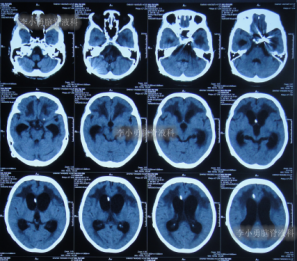

在李小勇主任的引领和培养下,一支技术过硬、敢于担当的医疗团队迅速成长。王光主任作为团队的核心骨干,深得李小勇主任技术精髓,在脑脊液引流、感染控制和围手术期管理方面经验丰富。他介绍,此次救治的71岁女性患者,情况就非常典型且危重。该患者因脑出血、动脉瘤术后继发脑积水,在外院接受了脑室腹腔分流术后,不仅症状未缓解,反而迅速恶化,出现持续昏迷、高热,复查发现脑积水进行性加重,生命垂危。经病友推荐,家属带着最后一线希望,于2021年9月将患者送至北京医大中西医结合医院脑脊液科。“患者来时意识不清,肺部有严重感染,右侧肢体偏瘫,脑积水的‘闸门’——分流管,很可能已经失效甚至成为感染源。”王光主任回忆道。面对这个“烂摊子”,科室迅速启动疑难病例讨论。在李小勇主任的总体指导下,以王光主任为主力的治疗组,为患者制定了周密的“三步走”方案。

入院第二天,李小勇主任团队就为患者实施了手术,拔除了那根可能已被细菌“占据”的旧分流管,清除了感染源,并重新建立了精准、可控的脑室外引流通道。这根新的“生命管道”如同为肿胀的大脑打开了一扇“减压窗”,颅内高压迅速得到缓解。

引流是基础,但战胜感染、改善患者全身状况才是康复的关键。在持续引流的同时,团队根据药敏结果使用敏感抗生素,并辅以营养神经、维持水电解质平衡、强化肺部分泌物引流等综合支持治疗。在医护人员的精心照料下,患者的体温逐渐恢复正常,意识从昏迷转为清醒,肺部感染也被有效控制。经过长达76天的精心准备,患者脑室缩小,颅内压力稳定,全身感染征象完全消失。此时,植入新分流管的最佳时机已然成熟。李小勇主任团队为患者成功实施了新的脑室腹腔分流术。这一次,分流系统在清洁、稳定的环境中开始正常工作。